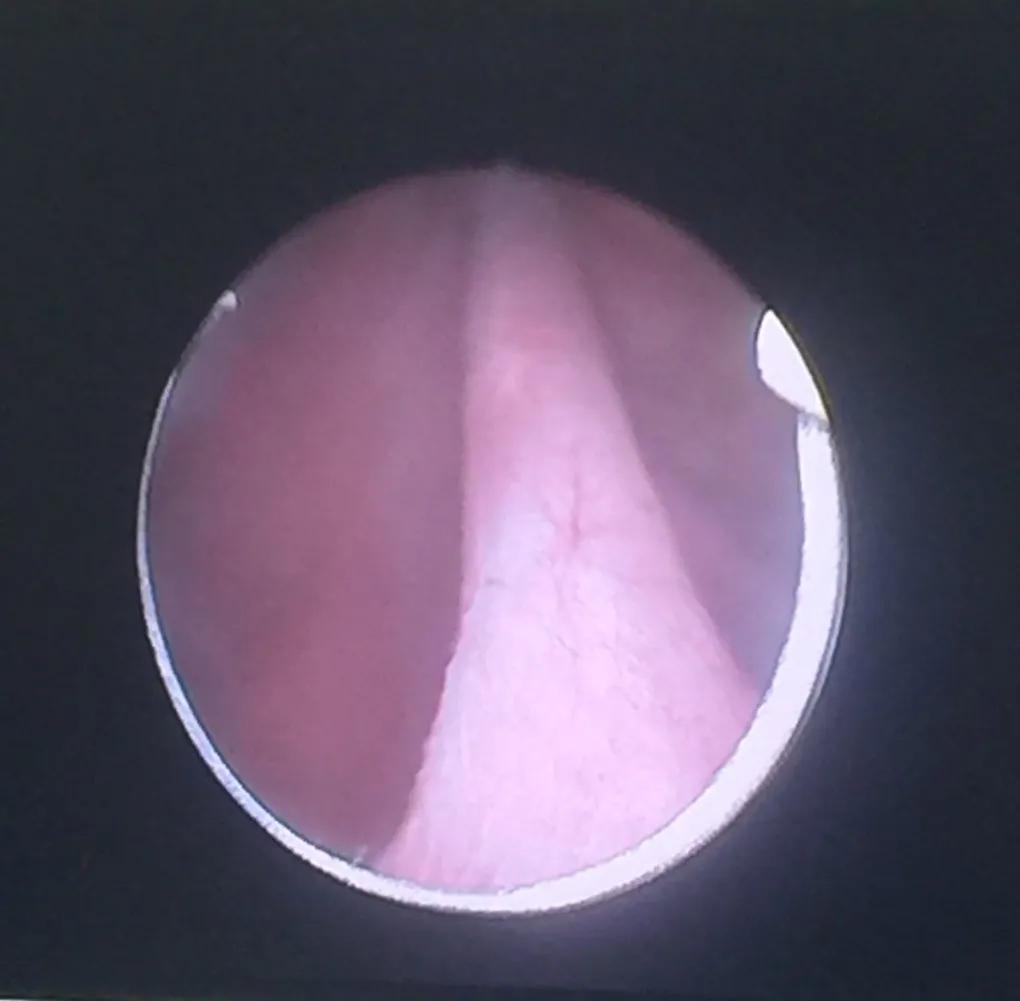

通过术前准备,今日在硬膜外麻醉下进行两种原创性新手术治疗。首先进行张家华教授发明的“直径匹配性递增性尿道内切开术”,术中发现“复杂性前尿道狭窄”,长度2.5厘米,F14小号尿道内切开镜不能通过(图一),插入0.8毫米导丝后,分别用F14小号、F20中号、F24大号尿道内切开镜,直角针状电极,纵行切开前尿道狭窄段。然后进行张家华教授发明的“张氏膀胱颈成形术”,术中发现膀胱颈挛缩仅有2毫米小孔(图二),F14小号尿道内切开镜不能通过,用直角针状电极纵行切开5点位、7点位、12点位三条纵沟,换F26电切镜再次切开膀胱颈,进入膀胱,发现膀胱有树根状小梁形成(图三)用琴弦状电极电切新鲜创面凸起组织,挤压膀胱,排尿通畅,留置F22导尿管。根据我们的经验,一个月后拔管,扩张尿道4—5次,康复治疗7天即将治愈,复发率仅仅2—5%(国内外其它医院的通行冷刀尿道内切开术和激光尿道内切开术复发率40—50%,膀胱颈电切术复发率30—40%)。

图一 前尿道狭窄